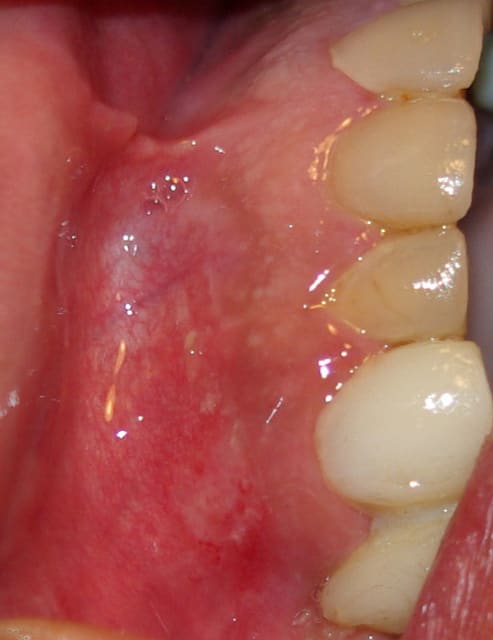

La lésion semble bulleuse devenant érosive érythémateuse recouverte des lambeaux persistants blanchâtres du toit de la bulle. De taille environ 1cm de diamètre. Entourée au départ de petites bulles transparentes encore intactes.

J'ai revu le patient aujourd'hui, l'état général est amélioré mais les douleurs n'ont pas diminué limitant l'alimentation. La lésion ne semble plus être vésiculeuse, elle forme un placard blanchâtre sur un fond érythémateux mais le raclage est rendu difficile car très douloureux, je pensais à une candidose mais la couche blanchâtre ne semble pas s'éliminer et la lésion est isolée et ne semble pas s'étendre.

En même temps l'aspect me ferait bien penser à un lichen...

Pour l'instant je penche vraiment vers le lichen plan...

l'absence d'ADP élimine les infections virales (zona, herpès, HIV). l'absence de l'induration (à confirmer) et saignement au contact (pour l'instant) éliminent l'ulcération néoplasique, mais à surveiller vu le contexte alcoolo-tabagique.

- ulcération traumatique ?, masquant une autre cause (l'état des racines du bridge provisoire)Rx

- pemphigus vulgaire? biopsie